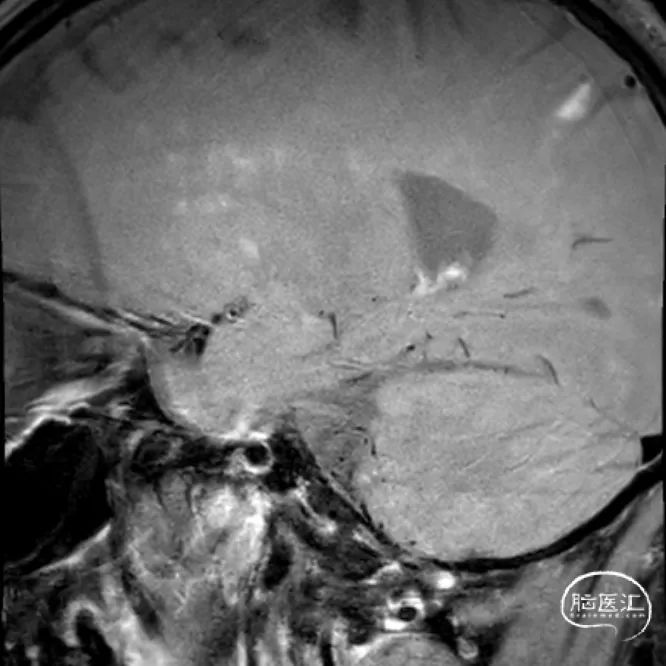

撤出微导丝后,经Fastunnel®输送型球囊扩张导管送入3.0mm*16mm NeuroStellar®颅内支架,支架到位后调整释放张力后定位支架。

术中缓慢释放NeuroStellar®颅内支架头端后系统稳定,随后释放至支架尾端,造影提示支架打开满意,贴壁满意。

最后经6F中间导管正侧位造影留存影像后结束手术。